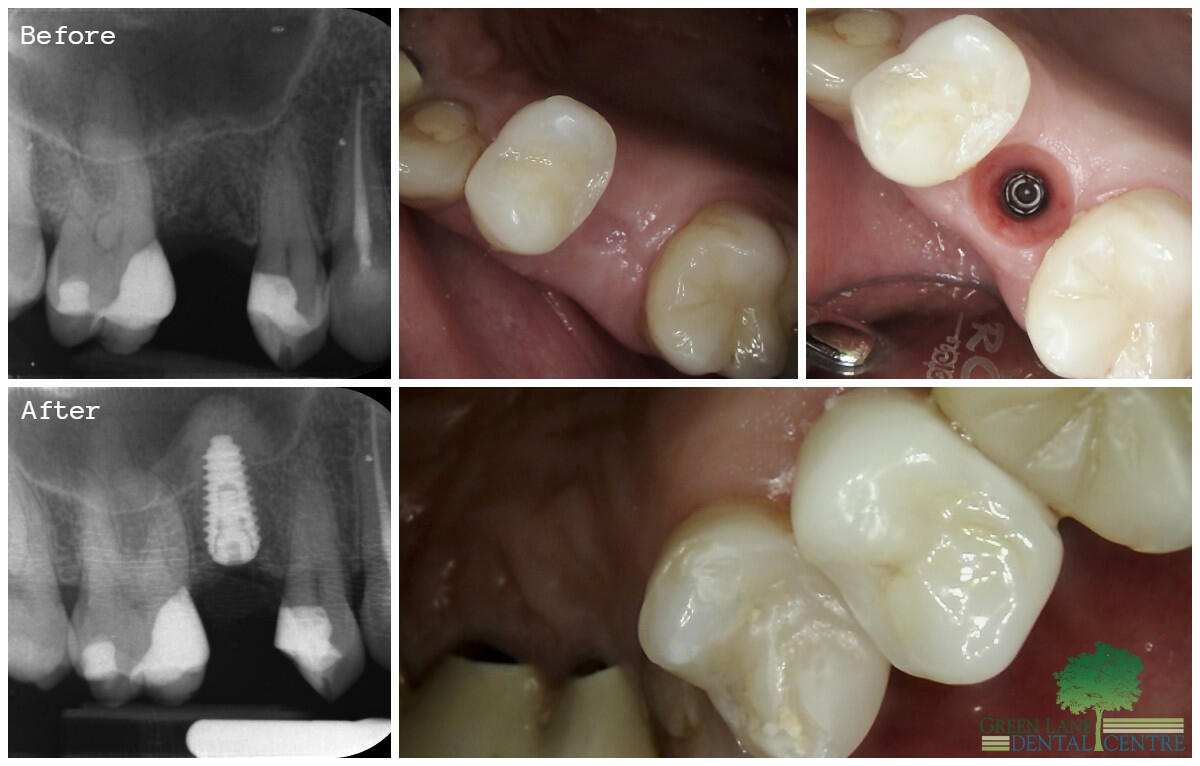

Smile Gallery